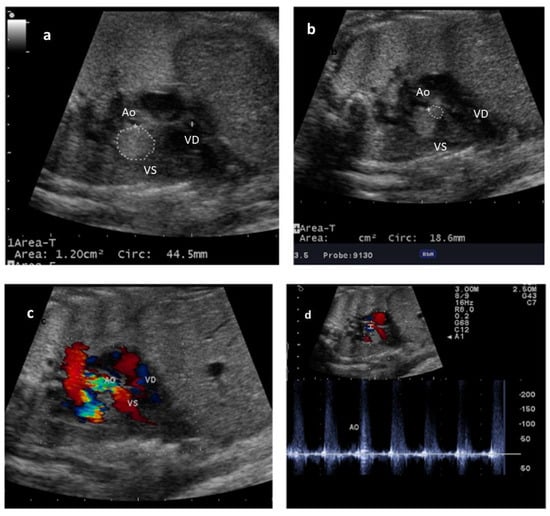

2. Case Report